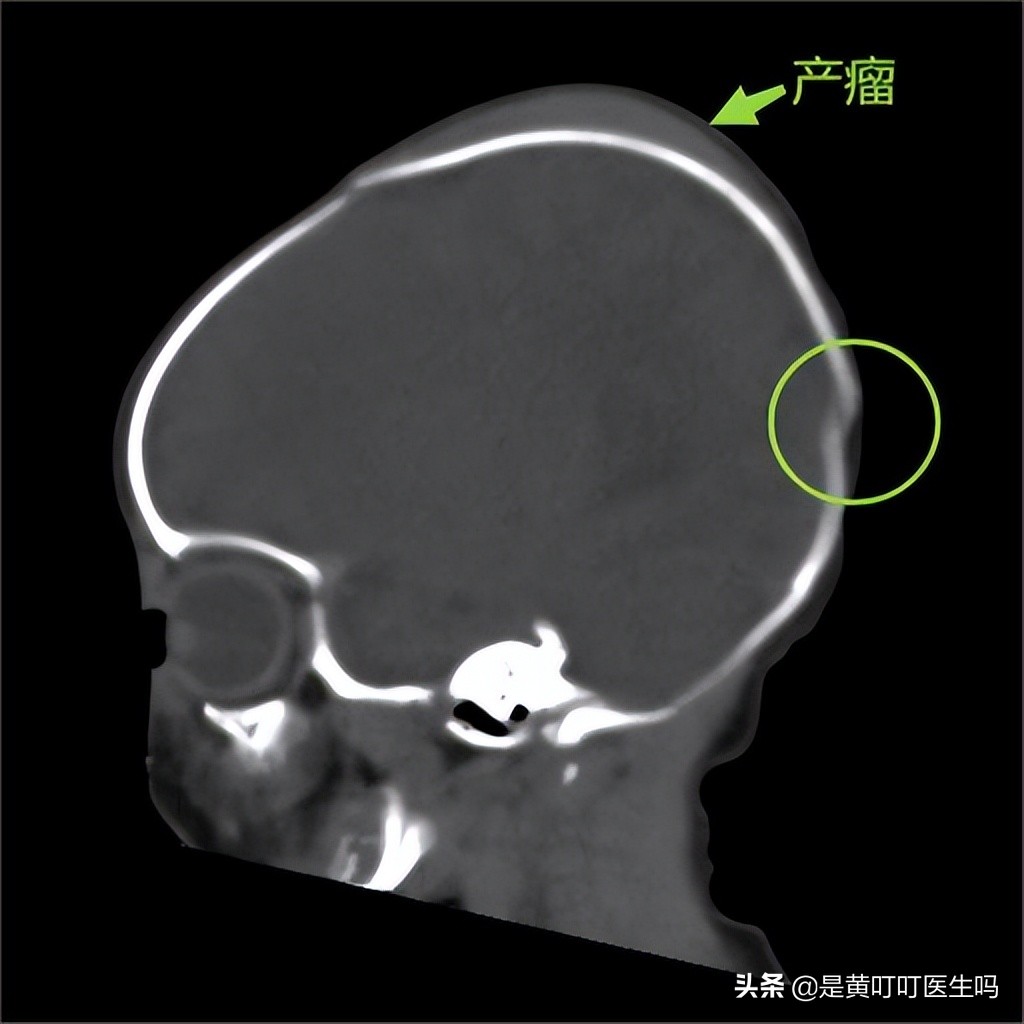

新生儿出生时,受到母体子宫收缩及产道的挤压,宝宝头顶左右侧或后侧出现的瘤样隆起,医学上称为产瘤。

在分娩过程中,当胎头到达母体骨盆底时,胎头受压使得颅骨重叠,以使胎头拉长变形以利于分娩,其中在胎头最前面的部分受压最大,若胎头过度受压致使局部血液循环不佳,最终导致头皮水肿、淤血等情况,甚至可发生皮下血肿。

圆圈标记处为颅骨重叠